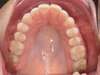

Avant

Après